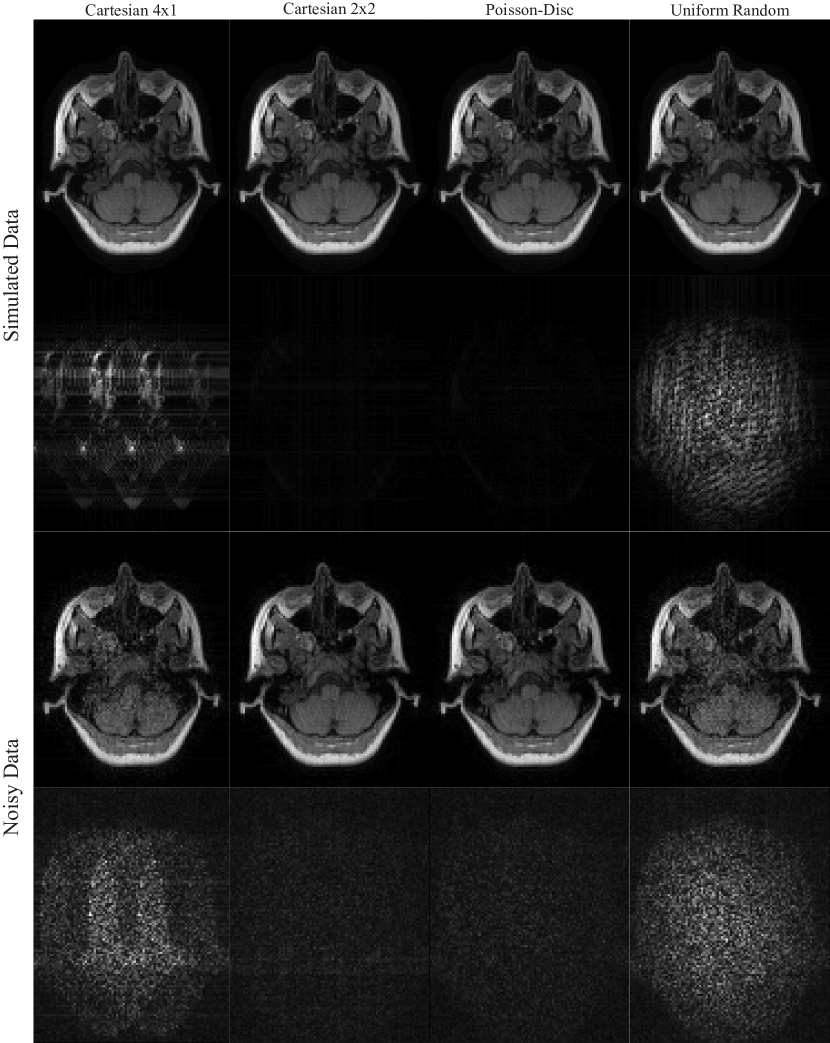

Refer to caption

Figure 2: Top row: Spatial sensitivity maps for each channel of the receive coil (limited to the support of the object). Bottom row: Corresponding coil images computed by Fourier transform of each channel of the fully-sampled data. Right: Combined image computed as the pixel-wise root of the sum of absolute squares of all coil images.

Figure 2 shows the coil image and the corresponding sensitivity map for all receive channels as well as the combined image. Figure 3 shows the combined power function and the Frobenius norm of the cardinal functions for different sampling patterns. While for Cartesian 2×2222\times 2 and Poisson-disc sampling the power function is small everywhere inside the sampled region indicating that interpolation error is small, the situation is different for Cartesian 4×1414\times 1 and uniform random sampling: Where larger gaps appear in the sampling pattern, the power function has high values. The power functions themselves are bounded by the diagonal elements of the kernel. This bound is approached in regions where the cardinal functions go to zero, i.e. far from acquired samples, and corresponds to a situation where nothing is known about the k-space value. The bound for the combined power functions is 6.55306.55306.5530 for the kernel used here. Consistent with this upper bound, the maximum values observed near the boundary in the computed maps are 6.48026.48026.4802 for Cartesian 4×1414\times 1, 6.39216.39216.3921 for Cartesian 2×2222\times 2, 6.37976.37976.3797 for Poisson-disc, and 6.42776.42776.4277 for uniform random sampling. Computing the maximum in a smaller inner region of size 305×230305230305\times 230 far from the boundary, the maximum values are 0.61540.61540.6154, 0.052520.052520.05252, 0.10870.10870.1087, and 4.33034.33034.3303, respectively. The last number highlights the fact that high values are attained even inside the sampled area for uniform random sampling. While the error bound for Poisson-disc sampling is twice as large as for the Cartesian 2×2222\times 2 pattern, it is still very small, i.e. 60×60\times smaller than the maximum which is obtained in unsampled regions. The reconstruction results (Fig. 4) for noise-less data confirm that the interpolation error is lower for Cartesian and Poisson-disc than for uniform random sampling. Cartesian 4×1414\times 1 performs worse than Cartesian 2×2222\times 2, confirming the notion that it is usually better to distribute the acceleration along different phase-encoding directions. The structure of the error maps in k-space is predicted well by the power function for all sampling patterns (Fig. 5). It has to be noted that the power function yields only a worst-case bound (scaled by the norm of the data) which depends on the sampling pattern, but not on the actual signal. In contrast, the actual error values in k-space depend on the energy distribution of the signal and are much higher in the k-space center than in the periphery.